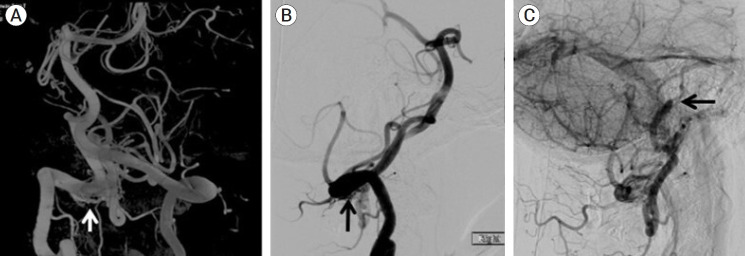

摘要椎动脉硬膜动静脉瘘是一种罕见的疾病。我们报告了一位有晕厥前症状的患者,发现在脑膜后动脉和流入乙状窦的皮质静脉之间有VADAVF。患者最初接受了手术干预,但未能消除分流。使用分流器的血管内治疗提供了明确的分流断开。

Vertebral artery dural arteriovenous fistulae (VADAVF) are a rare entity. We present a patient who experienced pre-syncopal symptoms and was found to have a VADAVF between the posterior meningeal artery and a cortical vein draining into the sigmoid sinus. The patient initially underwent surgical intervention, which failed to obliterate the shunt. Endovascular treatment with use of a flow diverter provided definitive disconnection of the shunt.